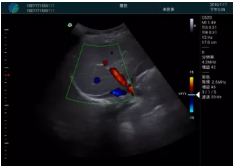

頸動(dòng)脈血流充盈飽滿,無外溢

肝內(nèi)血管顯示清晰,血流敏感無外溢